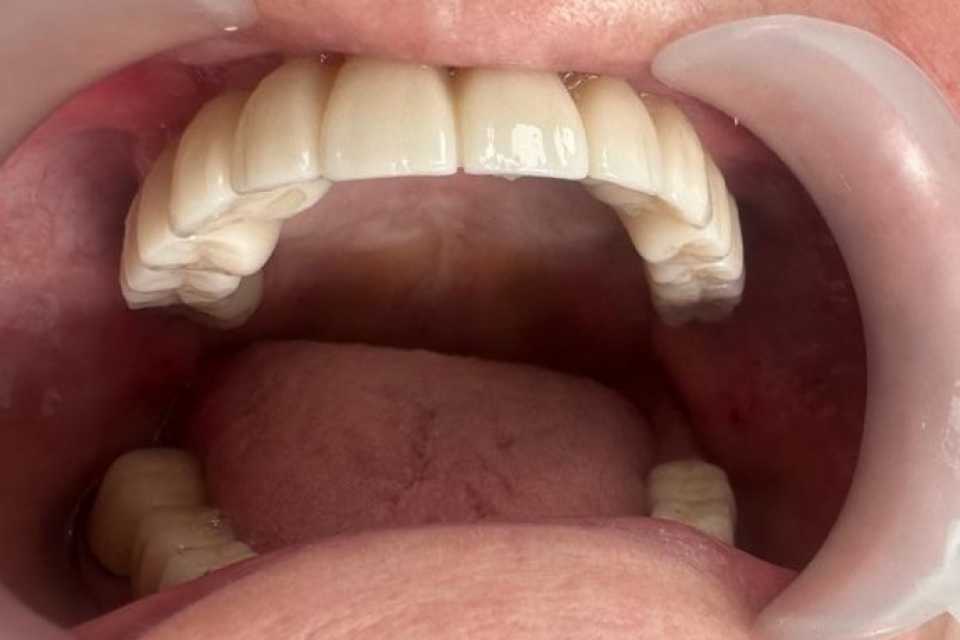

Sub anestezie generală s-au inserat 4 implanturi zigomatice și 2 implanturi pterigoide și 1 implant dentar normal cu ajutorul cărora am realizat o lucrare dentară protetică fixă din ceramica pe zirconiu insurubabila de 14 elemente.